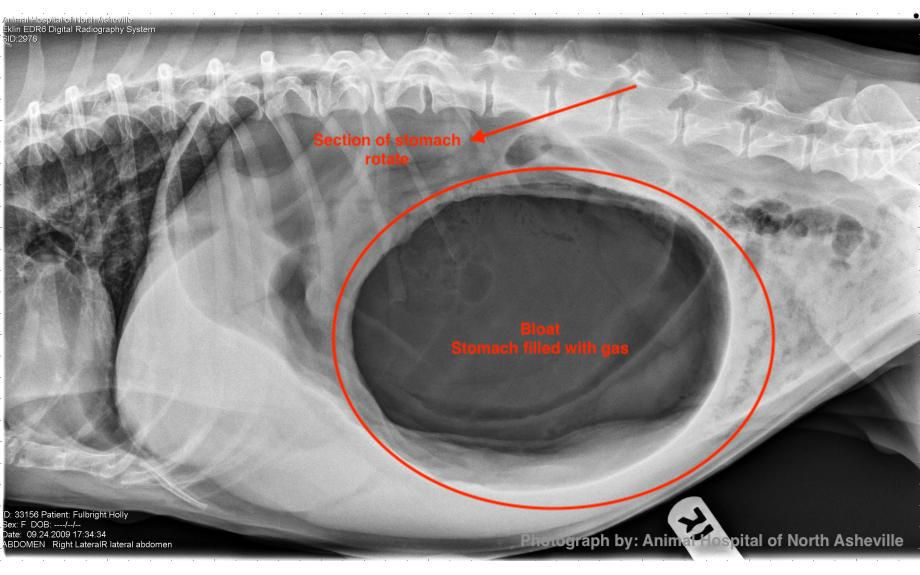

Dog Gastric Dilatation Treatment . This is where a dog's stomach rapidly fills up with gas and rotates or flips over on itself, resulting in the blockage of both the entrance and exit of the stomach. Whether done as part of surgical treatment of a gdv episode, or prophylactically in dogs that are considered to be high risk, attachment of the. Treatment is by debridement and repair of the gastric wall defect, followed by continued intensive supportive care. Gastric dilation and volvulus (gdv) is an enlargement of the stomach associated with rotation on the mesenteric axis.

From www.diagnosticmindset.com

Gastric dilatation or gastric volvulus in this dog? Dog Gastric Dilatation Treatment Treatment is by debridement and repair of the gastric wall defect, followed by continued intensive supportive care. This is where a dog's stomach rapidly fills up with gas and rotates or flips over on itself, resulting in the blockage of both the entrance and exit of the stomach. Gastric dilation and volvulus (gdv) is an enlargement of the stomach associated. Dog Gastric Dilatation Treatment.

Gastric dilatation or gastric volvulus in the radiographs of dogs? Dog Gastric Dilatation Treatment Treatment is by debridement and repair of the gastric wall defect, followed by continued intensive supportive care. Whether done as part of surgical treatment of a gdv episode, or prophylactically in dogs that are considered to be high risk, attachment of the. Gastric dilation and volvulus (gdv) is an enlargement of the stomach associated with rotation on the mesenteric axis.. Dog Gastric Dilatation Treatment.